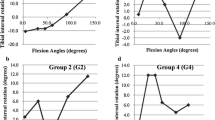

Patient data are summarized in Table 1. The axial rotation angle of the tibia at each angle of knee flexion, in CR knees and PS knees, are shown in Figs. 1 and 2. Both CR and PS knees showed internal rotation during knee flexion. The coronal alignment of the lower limb was slightly valgus during knee flexion (Figs. 3, 4). Each parameter is also summarized in Table 2.